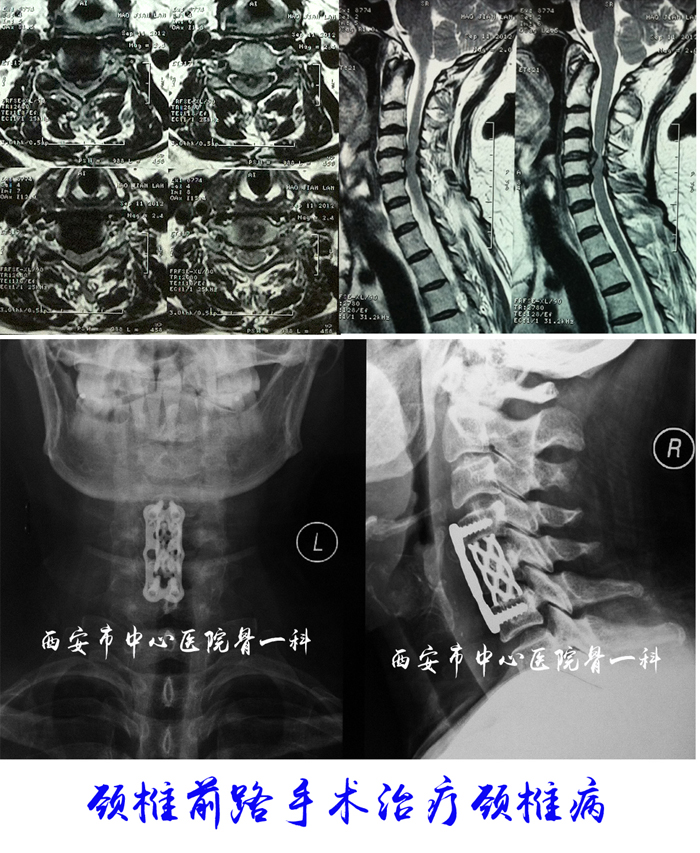

微创病例图片

颈椎病